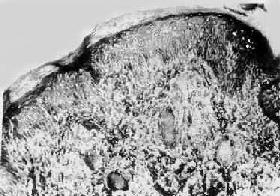

图18-17 结核样型麻风

真皮内有主由类上皮细胞构成的结节状病灶,其中可见Langhans细胞,颇似结核结节,但中央无干酪样坏死

(1)皮肤:病变多发生于面、四肢、肩、背和臀部皮肤,呈境界清晰、形状不规则的斑疹或中央略下陷、边缘略高起的丘疹。镜下,病灶为类似结核病的肉芽肿,散在于真皮浅层,有时病灶和表皮接触。肉芽肿成分主要为类上皮细胞,偶有Langhans巨细胞,周围有淋巴细胞浸润(图18-17)。病灶中央极少有干酪样坏死,抗酸染色一般不见抗酸菌。因病灶多围绕真皮小神经和皮肤附件,故引起局部感觉减退和闭汗。病变消退时,局部仅残留少许淋巴细胞或纤维化,最后,炎性细胞可完全消失。